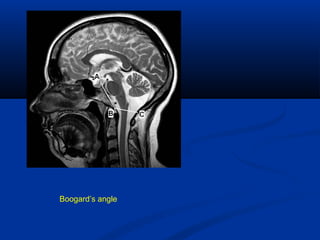

Boogard’s angleBoogard’s angle

Boogard ‘s Angle Angle intersected by

1st

line between Dorsum

sellae to Basion &

Mc Rae’s line.

119-1350

Average - 1220

> 1350

Basillar impression

Boogard’s angle